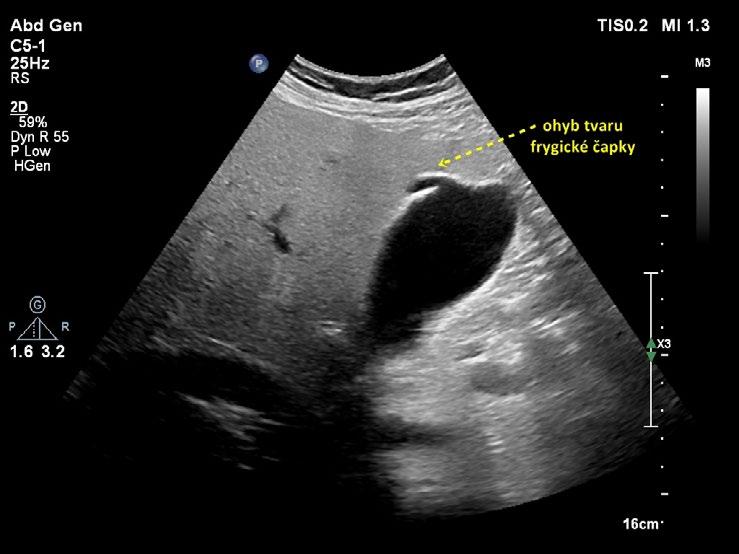

Překlopení fundu žlučníku vytváří obraz frygické čapky (obr. 1.10, obr. 1.11). Žlučník tvaru frygické čapky je relativně častý (až 6 %). Raritním nálezem je dvojlaločný žlučník nebo divertikl žlučníku.

Obr. 1.10 Žlučník tvaru frygické čapky

Obr. 1.11 Žlučník tvaru frygické čapky